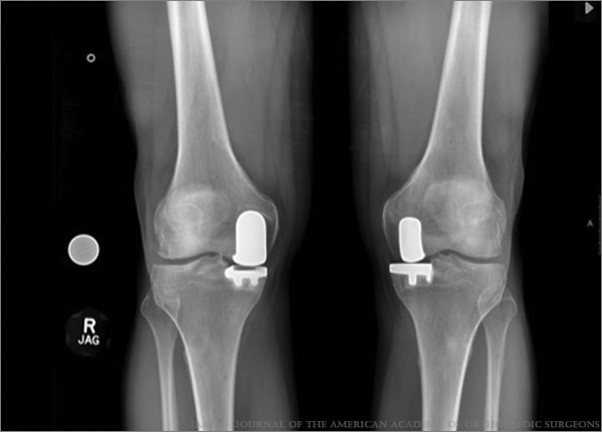

In both traditional and robotic-assisted joint replacement surgery, the damaged bone and cartilage are removed and replaced with prosthetic components.

- Only the damaged compartment is replaced in a partial (unicompartmental) knee replacement surgery, while healthy cartilage and bone and all of the ligaments are preserved.

- A joint replacement that is well-aligned and stable and that specifically minimizes the errors that can occur in patients who have unique variations in their joint anatomy

During the surgery, your surgeon will place navigation pins into your bone to guide the robotic-assisted instruments in space. The robotic instruments provide sensory feedback to assist the surgeon in precisely removing damaged bone and cartilage and replacing it with prosthetic (artificial) components.

The prosthetic components mimic the shape and movement of the joint. These are made of a combination of metal, plastic, and ceramics.